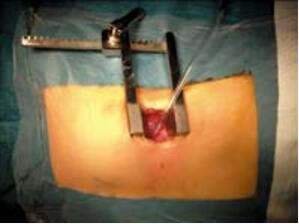

笔者第一次遇到这种情况是在进行肌部室间隔缺损封堵时,传统的胸骨切口并不是封堵某些缺损的最佳入路。当然,可能通过旋转拖拉可以把心脏通过切口暴露出来,但是切口越小孩子越大越难操作。而且植入封堵器的直行方向会消失,从而导致封堵器超声图像形态变形。经食管超声心动图图像在心尖部卷曲的情况下也会变得复杂。对于这些病人,笔者设计了一种非常简单而且比标准方法更美观的手术,特别适用于极度靠近心脏前部几乎没有间隔边缘的心尖部缺损患者。患者向右旋转20~30度(图10-44),心脏上缘的探查借助经胸超声心动图进行,由第4 肋间入路(图10-45),此方法可以无需任何牵引精确到达心脏上部和室间沟,清晰的暴露穿刺位置。而且可以按照标准方法直接关闭任何心尖部缺损(图10-46,图10-47)。笔者提供的病例中有一个10月龄、10kg的患儿。选用 SQFDQ 9mm 封堵器封闭7mm的心尖部室间隔缺损。